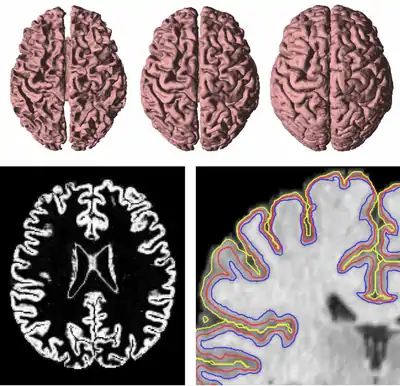

GVF has been used to find both inner, central, and central cortical surfaces in the analysis of brain images [5], as shown in Figure 4. The process first finds the inner surface using a three-dimensional geometric deformable model with conventional forces. Then the central surface is found by exploiting the central tendency property of GVF. In particular, the cortical membership function of the human brain cortex, derived using a fuzzy classifier, is used to compute GVF as if itself were a thick edge map. The computed GVF vectors point towards the center of the cortex and can then be used as external forces to drive the inner surface to the central surface. Finally, another geometric deformable model with conventional forces is used to drive the central surface to a position on the outer surface of the cortex.